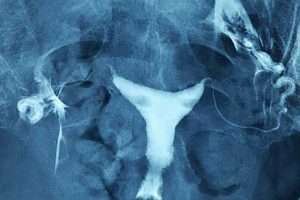

Myom

Rahim sağındaki iri myom kitlesi rahim boşluğu alt kısmının uzamasına ve sola doğru itilmesine sebep olmuş.